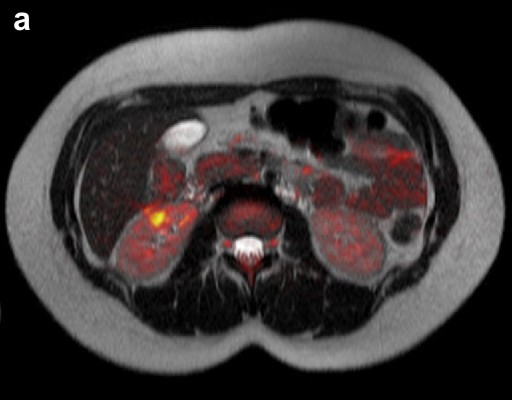

Given the lack of evidence of malignancy or infection, highly active antiretroviral therapy was resumed with a regimen including tenofovir, emtricitabine and boosted darunavir. Two months later, the patient was totally asymptomatic. She had had an undetectable HIV viral load. Lipase and CRP were within the normal range, and abnormal findings on MRI and FDG-PET/CT had totally disappeared at the level of the pancreas and were almost entirely normalized in the other sites (Figure 3).

Figure 3. Image following highly active antiretroviral therapy. a. Fusion of axial MRI T2-weighted spin-echo and diffusion-weighted images showing complete resolution of the pancreatic lesions and dramatic regression of the right kidney lesion. b. Axial MRCP showing improvement of the main pancreatic duct abnormalities. c. FDG-PET/CT revealing slight residual radiotracer uptake in the axillary lymph nodes. |